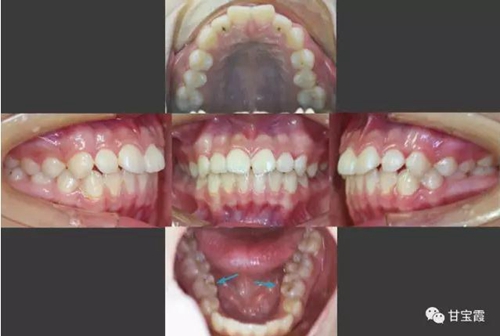

于是我們決定拔出滯留的下頜乳牙和上頜的兩顆第一雙尖牙。

3.jpg

矯正中排齊并內(nèi)收上下前牙,同時也適當(dāng)?shù)那耙屏讼骂M后牙,關(guān)閉了所有的拔牙間隙,患者長大以后也不必要再鑲牙了。

4.jpg